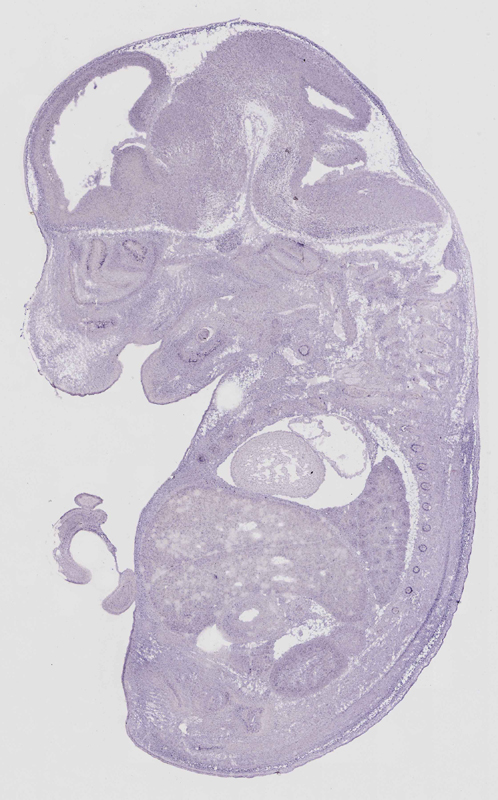

euxassay_003318_07:

embryonic day 14.5

Specimen

euxassay_003318_08: